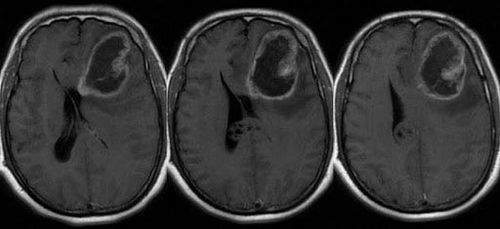

Chẩn đoán u nguyên bào thần kinh đệm

U não tiên phát ác tính vẫn là một thách thức trong y khoa. U nguyên bào thần kinh đệm (còn gọi là u tế bào thần kinh đệm độ IV, u sao bào độ IV) là u não tiên phát phổ biến và ác tính nhất.